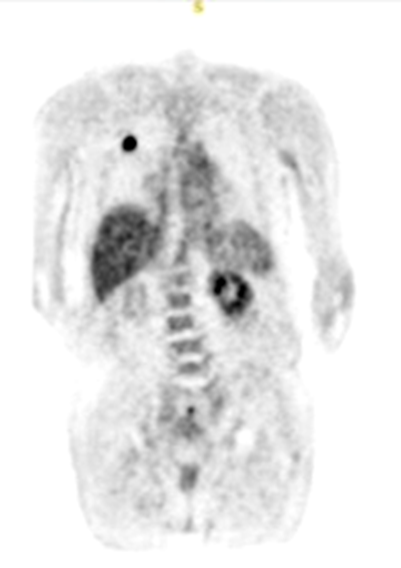

what does this image show

malignant single pulmonary nodule

benign single pulmonary nodule

what does this image show if the chest x-ray demonstrated a nodule in the right lung

increased metabolic activity indicative of malignancy

single pulmonary nodule (SPN)

how can you tell the difference between a malignant and benign single pulmonary nodule

malignant will have more uptake on a F-18 FDG scan